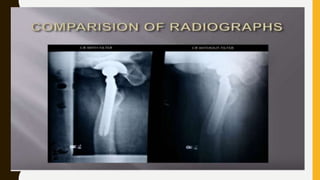

The document discusses the control of scattered radiation in X-ray imaging, covering topics such as types of scattered radiation, devices to limit beam exposure, and techniques for improving image quality. It highlights the disadvantages of scattered radiation and presents solutions like filters, collimators, and grids designed to enhance contrast and reduce patient radiation dose. The document also details various filtration methods and grid types that help minimize the impact of scatter on radiographic images.